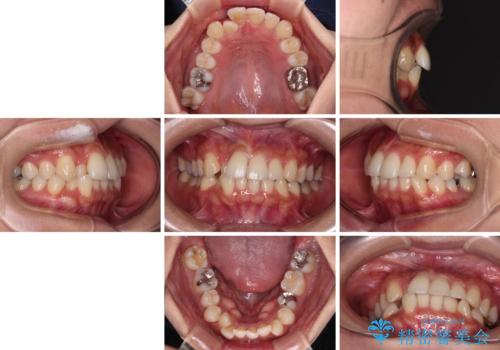

- 前歯のクロスバイトと口元の膨らんだ横顔の印象を気にして来院された患者様です。

ご本人の気にされている口元は、分析数値からするとそれほど突出しているものではありませんでした。

しかしながら。そのまま叢生を解消すると横顔が突出した印象になる可能性が高かったため、上下左右の小臼歯4本を抜歯して、ワイヤー装置にて矯正治療を行うこととしました。

上下左右の第一小臼歯4本を抜歯して治療を行うことがセオリーでしたが、左下は第二小臼歯が銀歯であったため、イレギュラーではありますが、そちらを抜歯しました。

その影響で治療期間は長くなりましたが、処置していない歯を保存することができました。